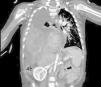

The evaluation included a thoracic radiograph (Fig. 1) that evinced pleural effusion and mediastinal shift and a blood panel that detected conjugated hyperbilirubinemia and transaminase elevation.